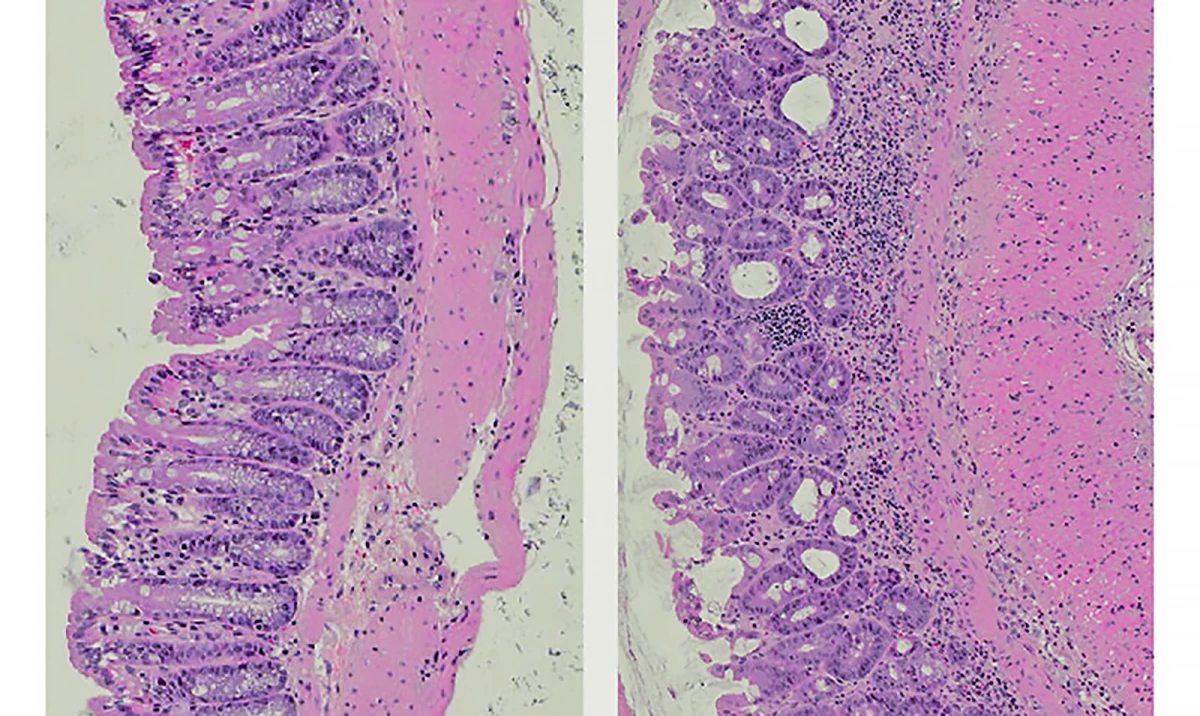

Crédito:Mice fed a normal diet (left) have healthy, well-organised gut tissues. The gut tissue of those fed a high-fat diet (right) is disrupted, with thickening of the gut wall (pink) and an accumulation of immune cells (purple dots) – clear signs of inflammatory bowel diseaseWEHI

“Pesquisadores alimentaram camundongos com uma dieta rica em gordura ou padrão por sete dias e descobriram que mesmo a exposição de curto prazo reduziu os níveis de IL-22, uma proteína vital para a integridade intestinal, controle da inflamação e reparo dos tecidos.“

“A IL-22 desempenha um papel vital na manutenção da saúde e da defesa intestinal”, explicou o autor principal e doutorando Le Xiong. “Sem a IL-22, o intestino fica vulnerável à inflamação. Apenas dois dias de uma dieta rica em gordura reduziram a IL-22 em camundongos, prejudicando a função intestinal antes mesmo do aparecimento de quaisquer sintomas.”